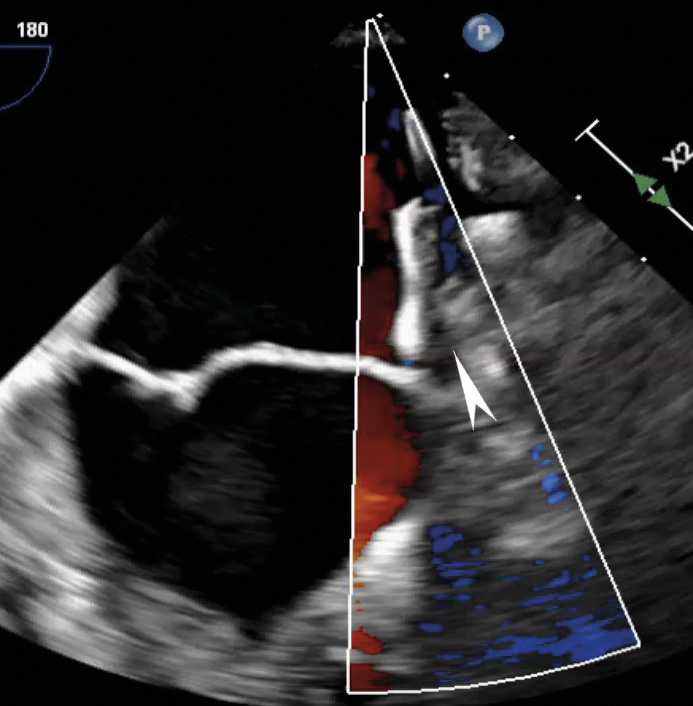

По результатам ЧП ЭхоКГ после вмешательства: в проекции МК визуализируется 1 клипса, митральная регургитация до 1-й степени (площадь струи регургитации 4,5 см2), величина коаптации менее 3 мм. Площадь отверстия МК – 4,7 см2. Кольцо МК = 3,45/3,8 см. Средний диастолический градиент на МК – 2,1 мм рт. ст. Место имплантации клипсы без особенностей. Количество струй регургитации – 1, тип регургитации – эксцентрический, распространяющийся вдоль межпредсердной перегородки. В просвете УЛП визуализируется плотно фиксированный окклюдер. Периферического кровотока по краям окклюдера не выявлено. В месте пункции межпредсердной перегородки визуализируется лево-правый сброс до 3 мм. Данные ЧП ЭхоКГ после вмешательства приведены на рис. 3–5.

Рис. 4. В режиме цветного доплеровского картирования патологического сброса и краевых потоков в проекции установленного окклюдера в ушке левого предсердия не выявлено (окклюдер указан стрелкой)

Рис. 5. В проекции митрального клапана лоцируется гиперэхогенная линейная структура – клипса (указано стрелкой). В режиме цветного доплеровского картирования регургитация до 1-й степени, средний градиент на митральном клапане 2 мм рт. ст.